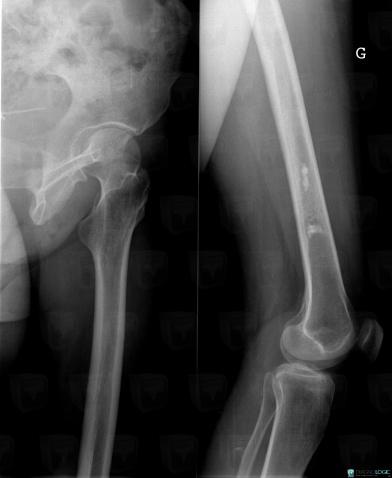

Infarctus osseux, Fémur -inférieur, Radio

Voici les informations spécifiques à l'image clé ci dessus:

- Diagnostic Infarctus osseux, Localisation(s) Fémur - 1/3 inférieur, comportant les gammes Condensation localisée unique, Lacune avec matrice calcifiée